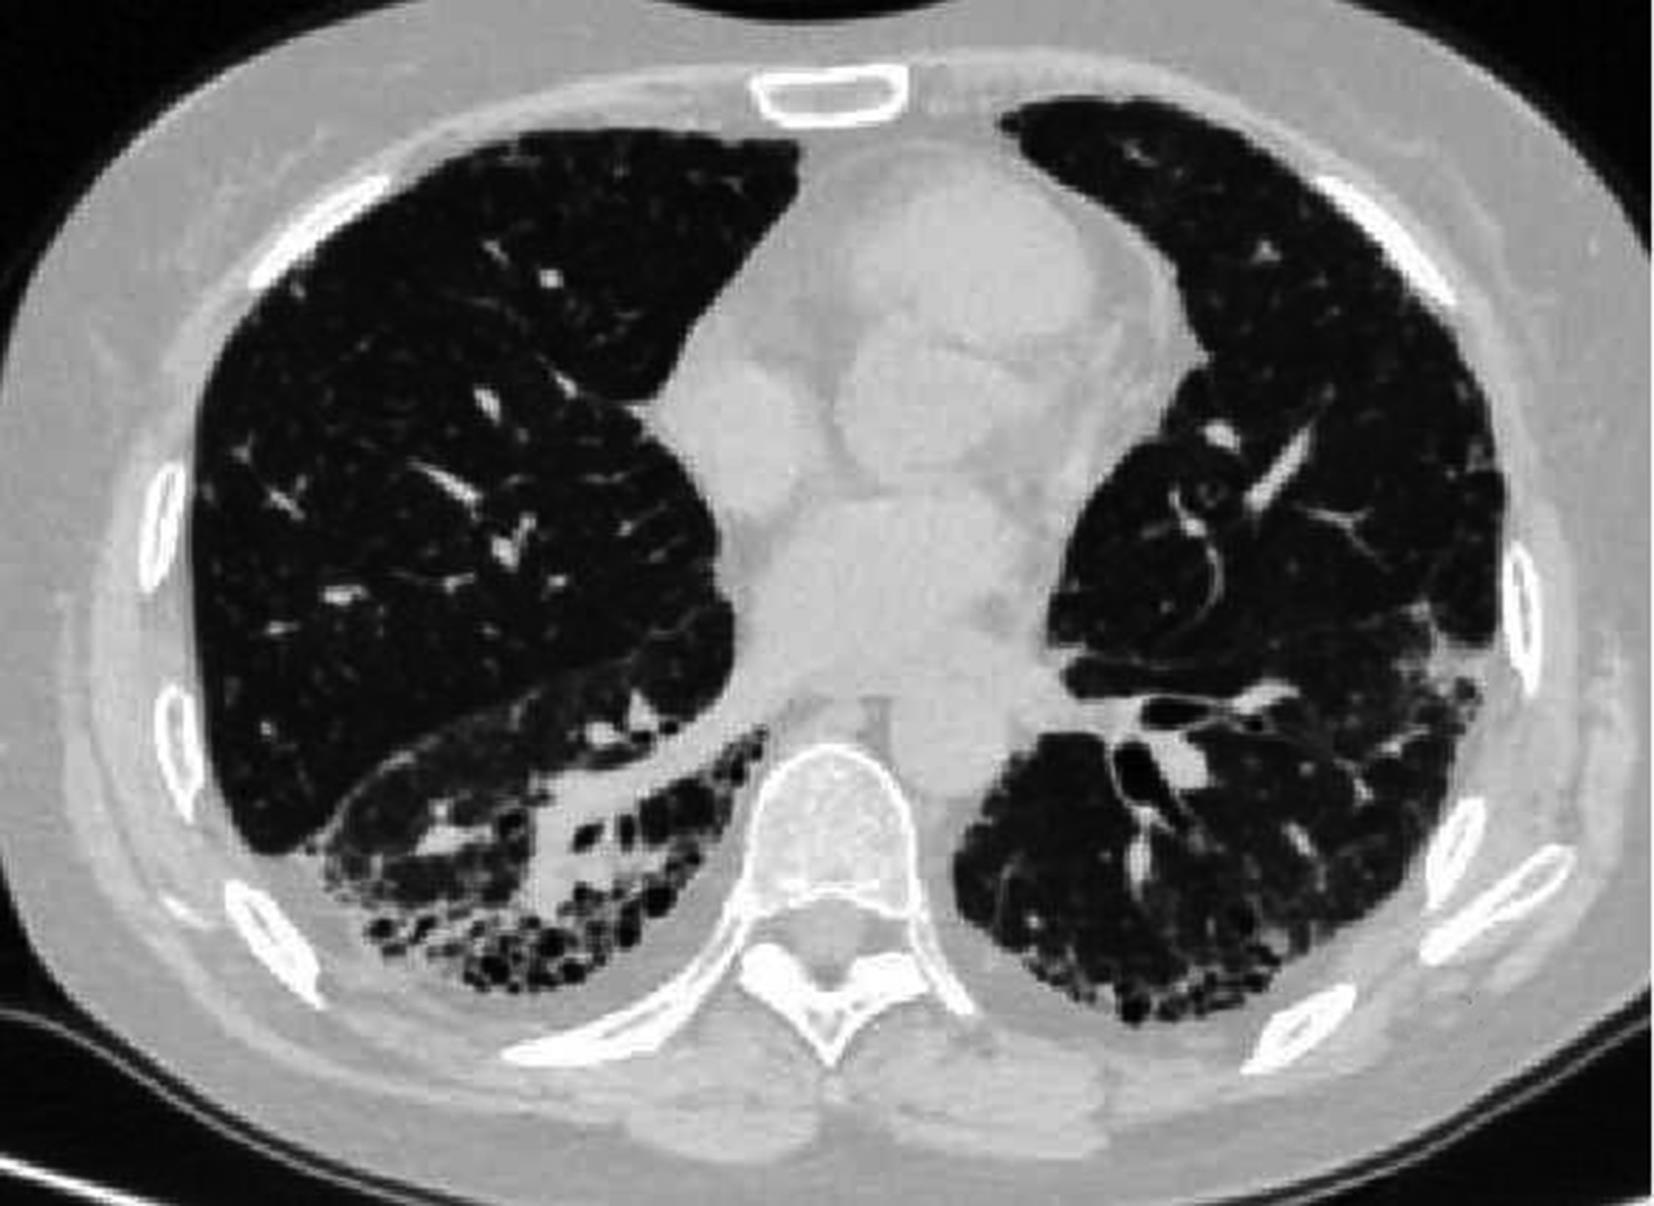

• 系统性红斑狼疮患者肺部影像学特征与疾病活动度相关性研究

2023, 48(11):1351-1355. DOI: 10.13406/j.cnki.cyxb.003353

摘要 (94) HTML (39) PDF 1.35 M (174) 评论 (0) 收藏

摘要:目的 探讨系统性红斑狼疮合并间质性肺病的CT特征与疾病活动度的相关性。方法 纳入131例系统性红斑狼疮相关间质性肺病患者。分析其疾病活动度评分、影像学特征及高分辨CT(high resolution computed tomography,HRCT)肺间质纤维化Kazerooni评分。采用Spearman秩和相关系数检验分析各评分之间的相关性。结果 Kazerooni评分法中的磨玻璃评分与系统性红斑狼疮疾病活动度-2000评分(systemic lupus erythematosus disease activity index-2000,SLEDAI-2000)呈正相关,差异有统计学意义(rs=0.388,P<0.001)。而纤维化评分与SLEDAI-2000评分之间差异无统计学意义(P=0.837)。弥漫性肺泡损伤(diffuse alveolar damage,DAD)组磨玻璃评分得分最高,寻常型间质性肺炎(usual interstitial pneumonia,UIP)组纤维化评分得分最高,差异有统计学意义(均P<0.001)。比较不同间质性肺病(interstitial lung disease,ILD)类型之间SLEDAI-2000评分差异无统计学意义(P>0.05)。结论 胸部HRCT可有助于更全面地评估系统性红斑狼疮疾病情况,对制定治疗方案具有重要意义。